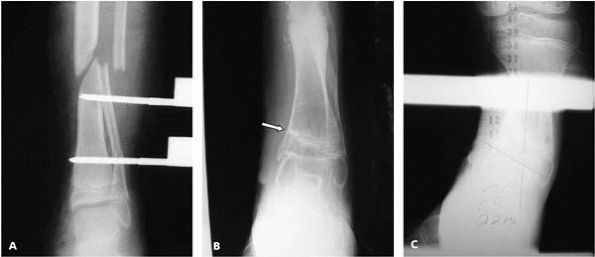

▪ FIGURE 9-16 A: Fixation for a medial malleolar fracture appears to be in acceptable position on a mortise radiograph of the ankle. B,C:

Lateral and oblique views demonstrate one screw is intra-articular. These views should have been obtained with intraoperative imaging to allow the screws to be replaced prior to leaving the operating room. |